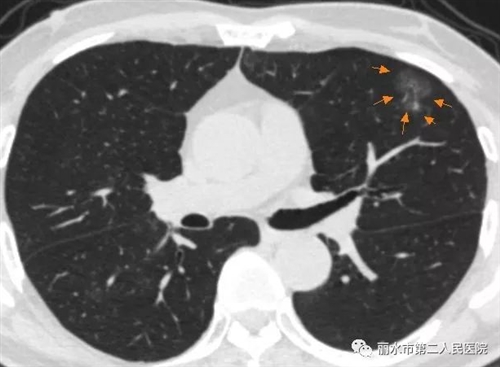

一般来说,肺内的良、恶性病变有时候均可以在肺部薄层CT影像上表现为磨玻璃结节,常见的原因可以是炎症、出血、不典型腺瘤样增生,当然也有可能是早期肺癌,包括原位癌、微浸润癌。

一般来讲,弥漫性生长的、边缘不清晰的、以纯磨玻璃表现为主的、短时间随访可消失的多数是良性病变;以局灶性生长为特征的、边缘清晰且伴有明显分叶、空泡、胸膜凹陷征、或病变内有明显实性成分的病变常提示恶性。